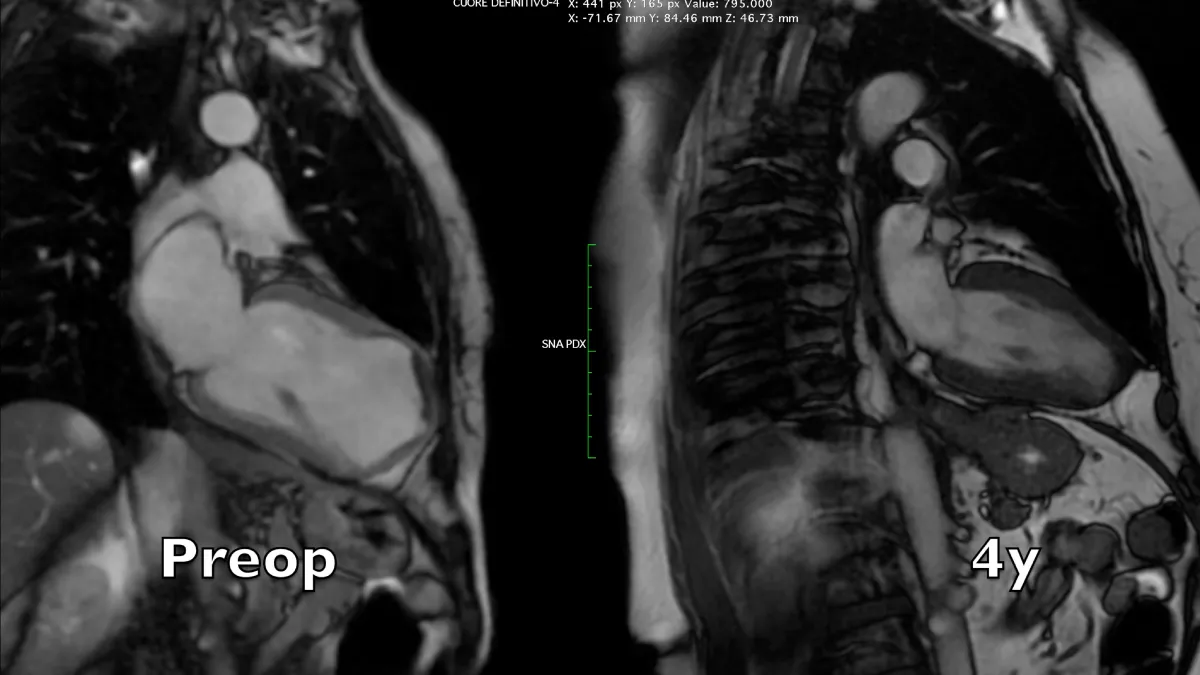

Figure 2: Magnetic resonance long axis systolic frames at two controls, preoperative and 4 years after the operation. A near-normal chamber geometry and wall thickening is evident. Note the reduction of left atrial volume, even in the absence of preoperative mitral regurgitation.

Video 2: Magnetic resonance four-chamber view, comparison between preoperative and 4 years controls.

Video 3: Magnetic resonance long axis view, comparison between preoperative and 4 years controls.

Figure 3: Magnetic resonance short axis systolic frames at two controls, preoperative and 4 years after the operation. The whole left ventricular chamber is restored and the remote myocardium regains its mechanics.

Preoperative imaging shows a very large dyskinetic region equal to around half of the ventricular chamber, conditioning a box-shaped ventricle with severely impaired global contraction, wall thickening, and diastolic function. Surgical reconstruction achieved an elliptic chamber with a normal volume and a new apex that were maintained along the years, gradually improving global ejection fraction and diastolic indices (Table 1), showing a positive remodeling induced by the optimised geometrical and functional parameters, left ventricular torsion included. Remote regions show a renewed, increased thickening granted by the better chamber geometry and fibers’ realignment, and the whole left ventricle shows a time-dependent restoration of its functional reserve, preoperatively hidden by the unfavourable functional conditions.

Apical region study (Figure 4 and Video 5) clearly demonstrates an improvement in apical geometry and rotation (from - 4.1 degrees to 4.6 degrees) in the immediate postoperative period induced by the surgically reoriented bundles of fibers. Consequently, left ventricular torsion improved to 7 degrees after the operation, with a reduction to about 4 degrees four years after surgery, due to a new-onset small apical dyskinetic area that reduces counterclockwise rotation to 1.3 degrees. Magnetic resonance short axis views (Figure 3 and Video 4) highlight the physiologically restored left ventricle along its whole length, from the apex to the base. The key surgical steps of this technique are: a) the septal rim of the suture is as long as the patch; b) the lateral rim of the suture shrinks the displaced fibers to a more physiologic orientation, given that it must adapt the dilated lateral wall onto the patch; c) a new apex is rebuilt (elliptic shape); d) a very small “akinetic” patch is used to bring closer the normal myocardium, redirecting fibers in a more physiologic disposition (Video 6).